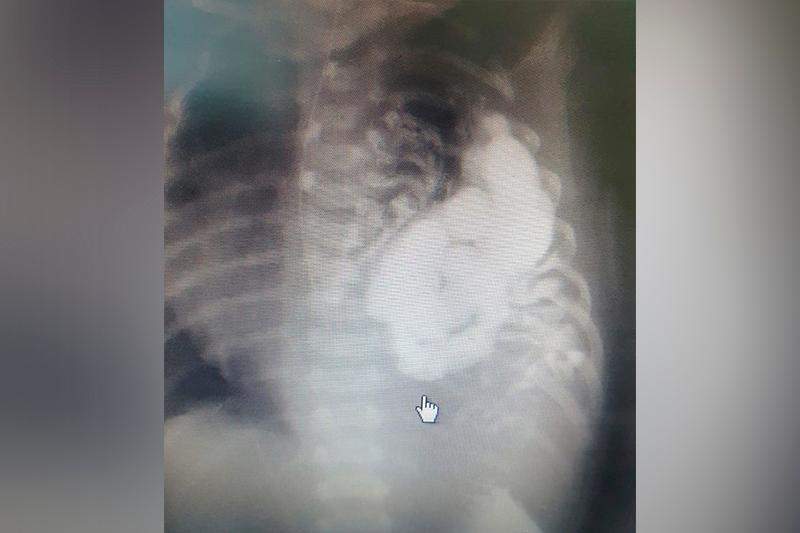

الماتى وبلىسىندا ىشەك قۇرىلىسى كەۋدە تۇسىندا ورنالاسقان ءسابي دۇنيەگە كەلدى

تالدىقورعان. قازاقپارات - الماتى وبلىسىندا ىشەك قۇرىلىسى كەۋدە تۇسىندا ورنالاسقان ءسابي دۇنيەگە كەلدى.

قىركۇيەكتىڭ 29- كۇنى سارقان اۋداندىق ورتالىق اۋرۋحاناسىندا ىشەك قۇرىلىسى كەۋدە تۇسىندا ورنالاسقان ءسابي دۇنيەگە كەلگەن. 30- قىركۇيەك كۇنى سابيگە دەرەۋ وتا جاسالىپ، بالانىڭ ىشەك قۇرىلىسى ورنىنا قويىلعان. ال 3- قازان كۇنى نارەستە كۋۆەز اپپاراتىمەن الماتى وبلىستىق بالالار اۋرۋحاناسىنا جەتكىزىلگەن.

«نارەستەنىڭ ىشەك قۇرىلىسى، كوك باۋىرى بارلىعى كەۋدە تۇسىنا جىلجىپ كەتىپ، وكپەنى قىسقان. قازىر بارلىق ورگاندار ءوز ورنىنا قويىلدى. بالاعا وتا ءساتتى جاسالدى. ءسابي قازىر رەانيماتسيادان حيرۋرگيا بولىمىنە شىعارىلدى. جۇما كۇنى اناسىمەن بىرگە ۇيىنە جىبەرەمىز دەپ جوسپارلاپ وتىرمىز»، - دەدى الماتى وبلىستىق بالالار اۋرۋحاناسىنىڭ باس دارىگەرى مارات دوسقاليەۆ.